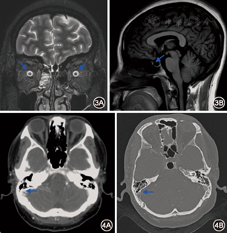

36例患者有26例(72.22%)有空蝶鞍(图3),10例(27.78%)有部分空蝶鞍;视神经均未见异常信号,视神经周围间隙均增宽(图3),10例(27.78%)视神经变细。

所有患者均行头CTV检查,15例(41.67%)怀疑有静脉窦血栓形成(图4)或静脉窦局部狭窄,6例(16.67%)有一侧静脉窦纤细。

15例CTV怀疑静脉窦血栓或狭窄的患者有10例(27.78%)行DSA检查,确诊静脉窦血栓形成2例(5.56%);静脉窦局部轻度狭窄7例(19.44%),但狭窄部位前后压力无差别;1例正常。